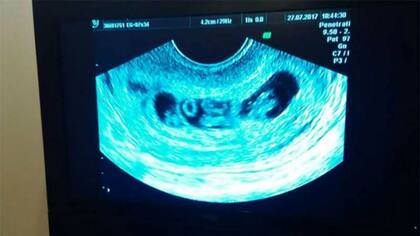

En la ecografía se puede ver claramente las tres bolsas, con los gemelos en una bolsa en el medio, mientras que los mellizos ocupan una bolsa cada uno en los extremos. El médico les juró no conocer ni haberse enterado de un caso así en el mundo.

Este embarazo múltiple se supo en los últimos días, cuando la pareja primeriza concurrió al médico para una ecografía. El médico, al ver el monitor, mientras Martín tomaba de la mano a Yanina, tan nervioso como ella, les preguntó si tenían antecedentes de mellizos en la familia. La pregunta disparó la mirada emocionada entre ellos, y antes de que pudieran contestar, el profesional les dijo “pero eso no es todo, hay más”.

“Fue entonces que el médico nos empezó a hacer escuchar los latidos: 1, 2, 3 y 4. Nos mirábamos con Martín y no teníamos explicación. Hasta el médico estaba shockeado”, comentó Yanina, quien cursa el tercer mes de embarazo, pero por su panza parece de seis meses, por lo que su médica le recomendó reposo absoluto.